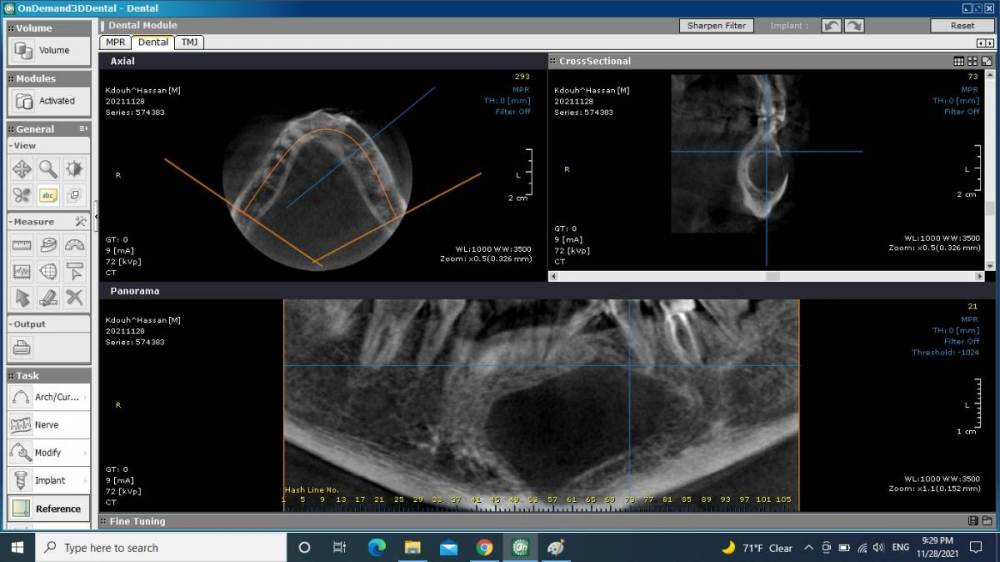

bilal Опубликовано 28 ноября, 2021 Поделиться Опубликовано 28 ноября, 2021 здравствуйте. какие вами деиствия при такой кисте, пациент пришел за имплантом на вч. витальность зубов непроверил пако Ссылка на комментарий

bilal Опубликовано 1 декабря, 2021 Автор Поделиться Опубликовано 1 декабря, 2021 ЗУБЫ ВИТАЛНЫЕ ВСЕ, ДУМАЮ РЕЗИДУАЛЬНАЯ КИСТА ОТ 34 ЗУБА, НАПРАВИЛ В ЧЛХ. Ссылка на комментарий